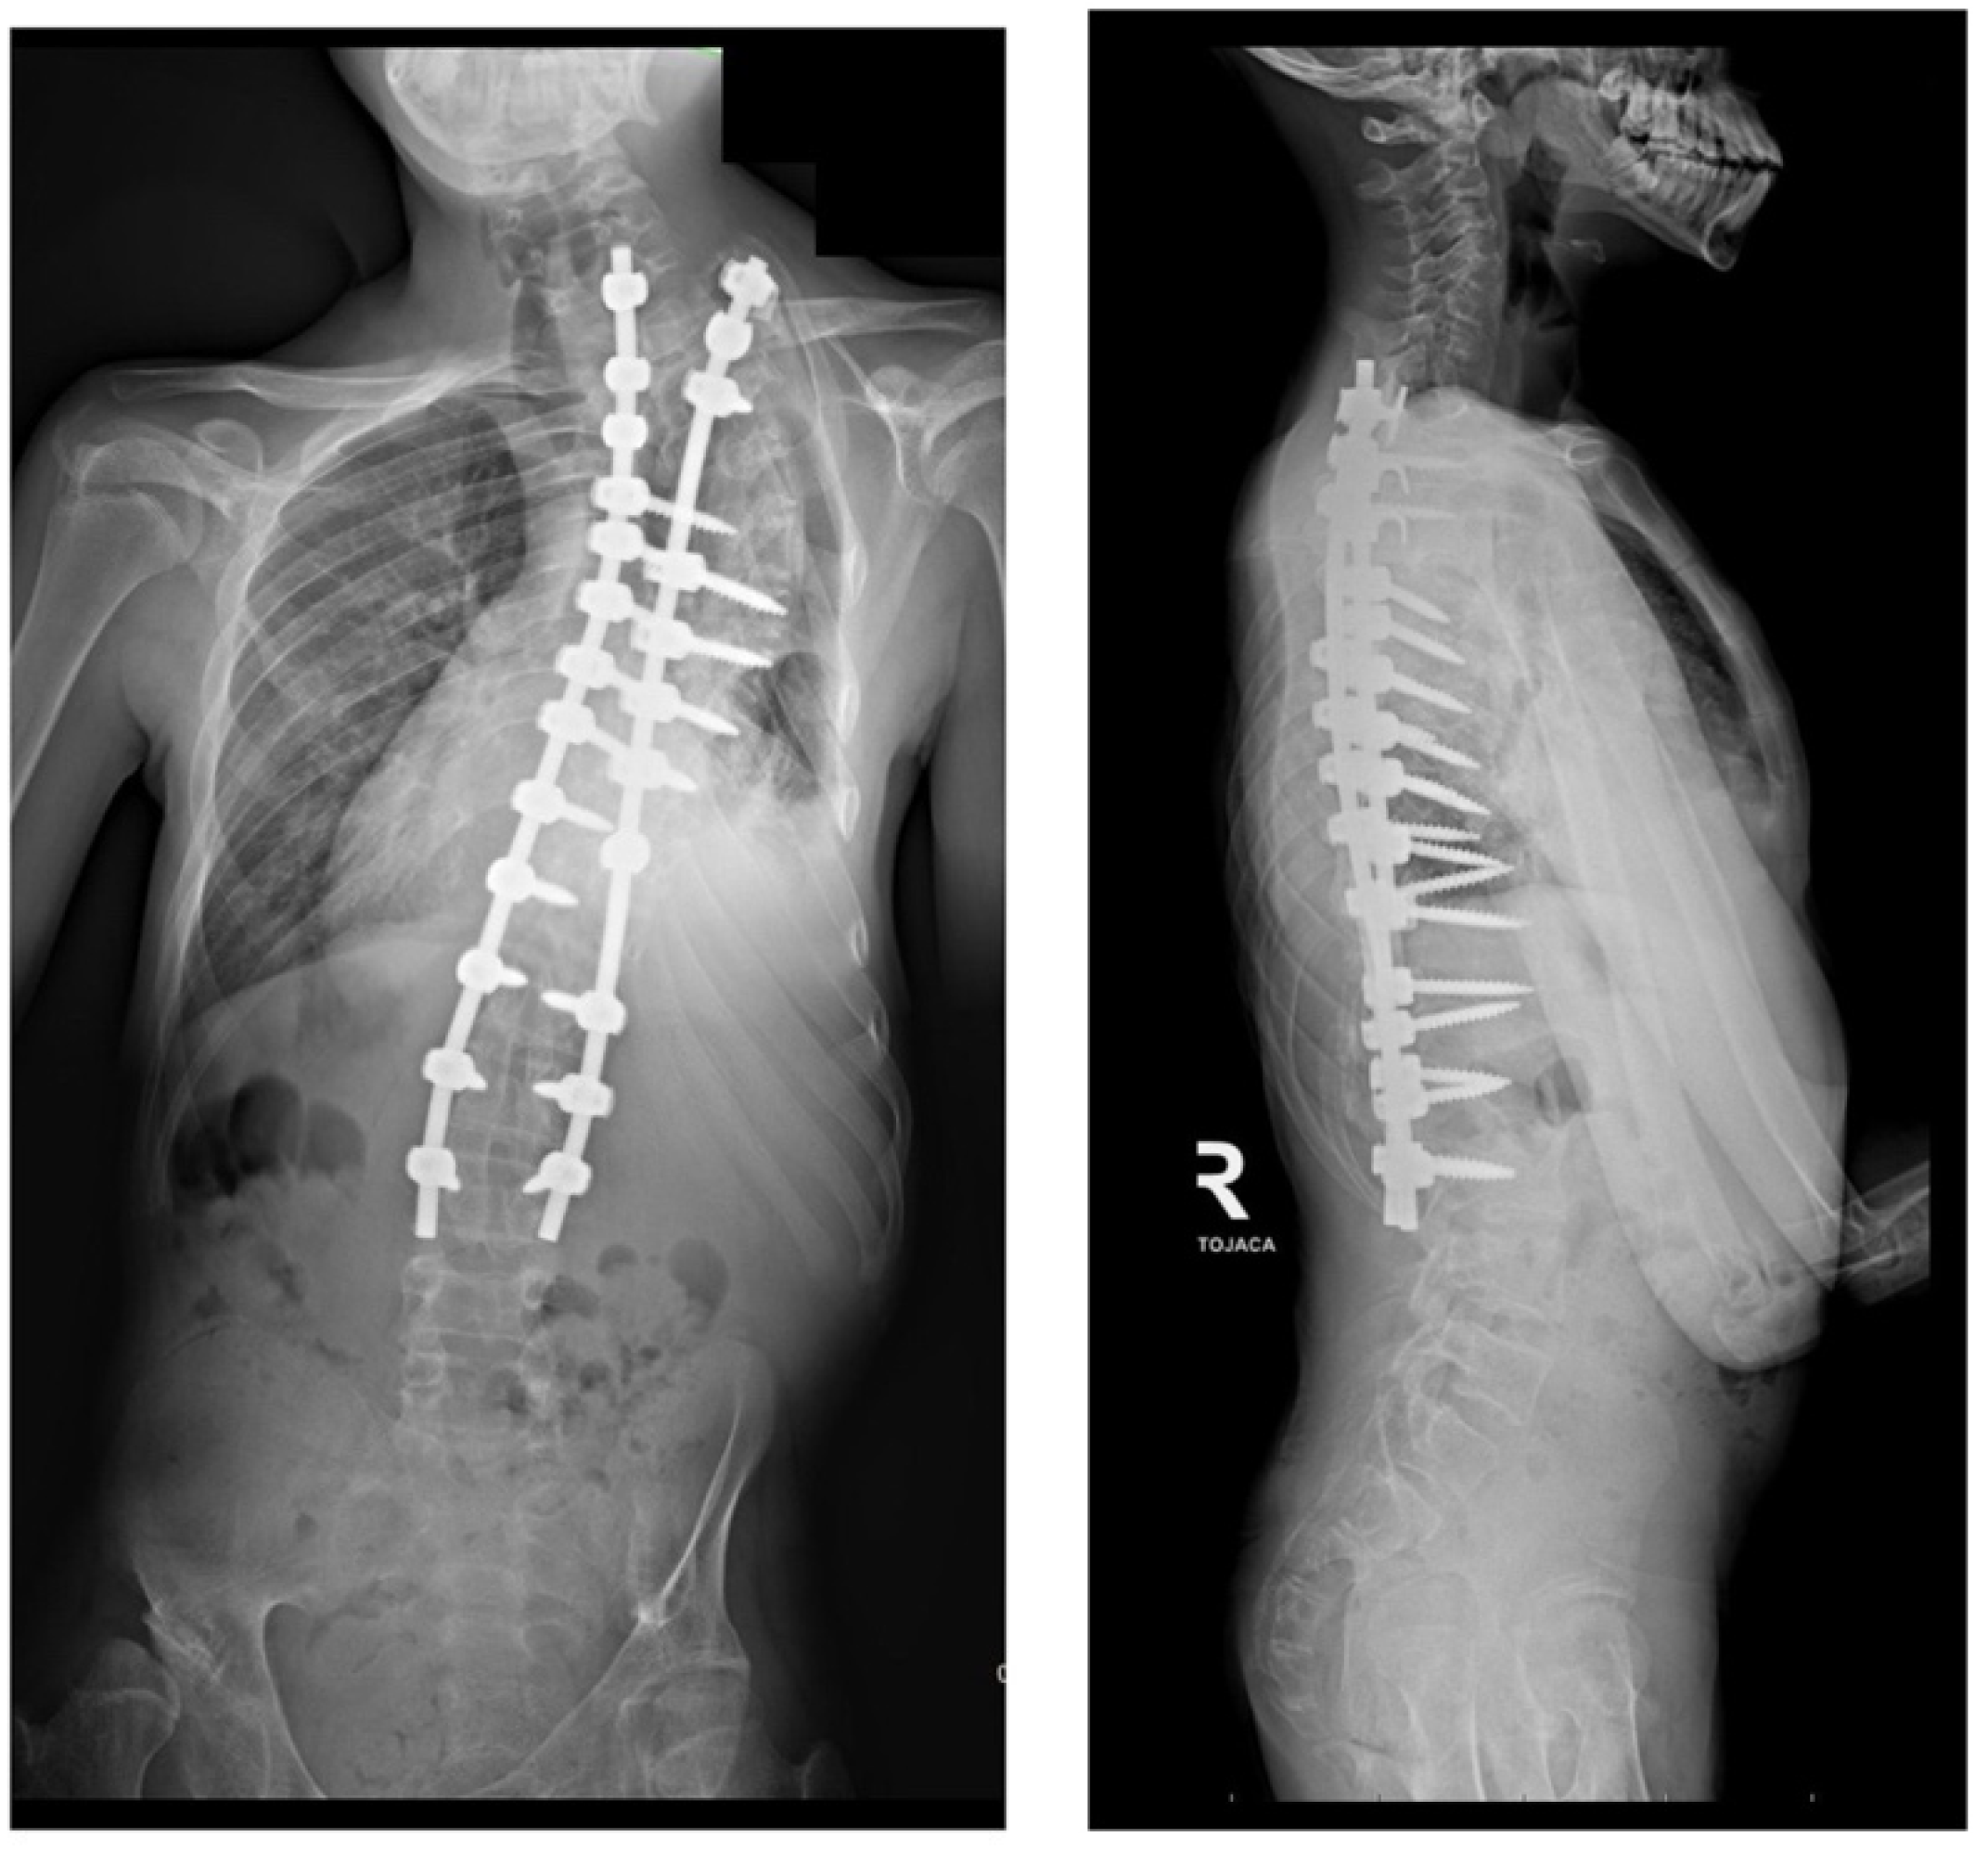

2. Case Presentation